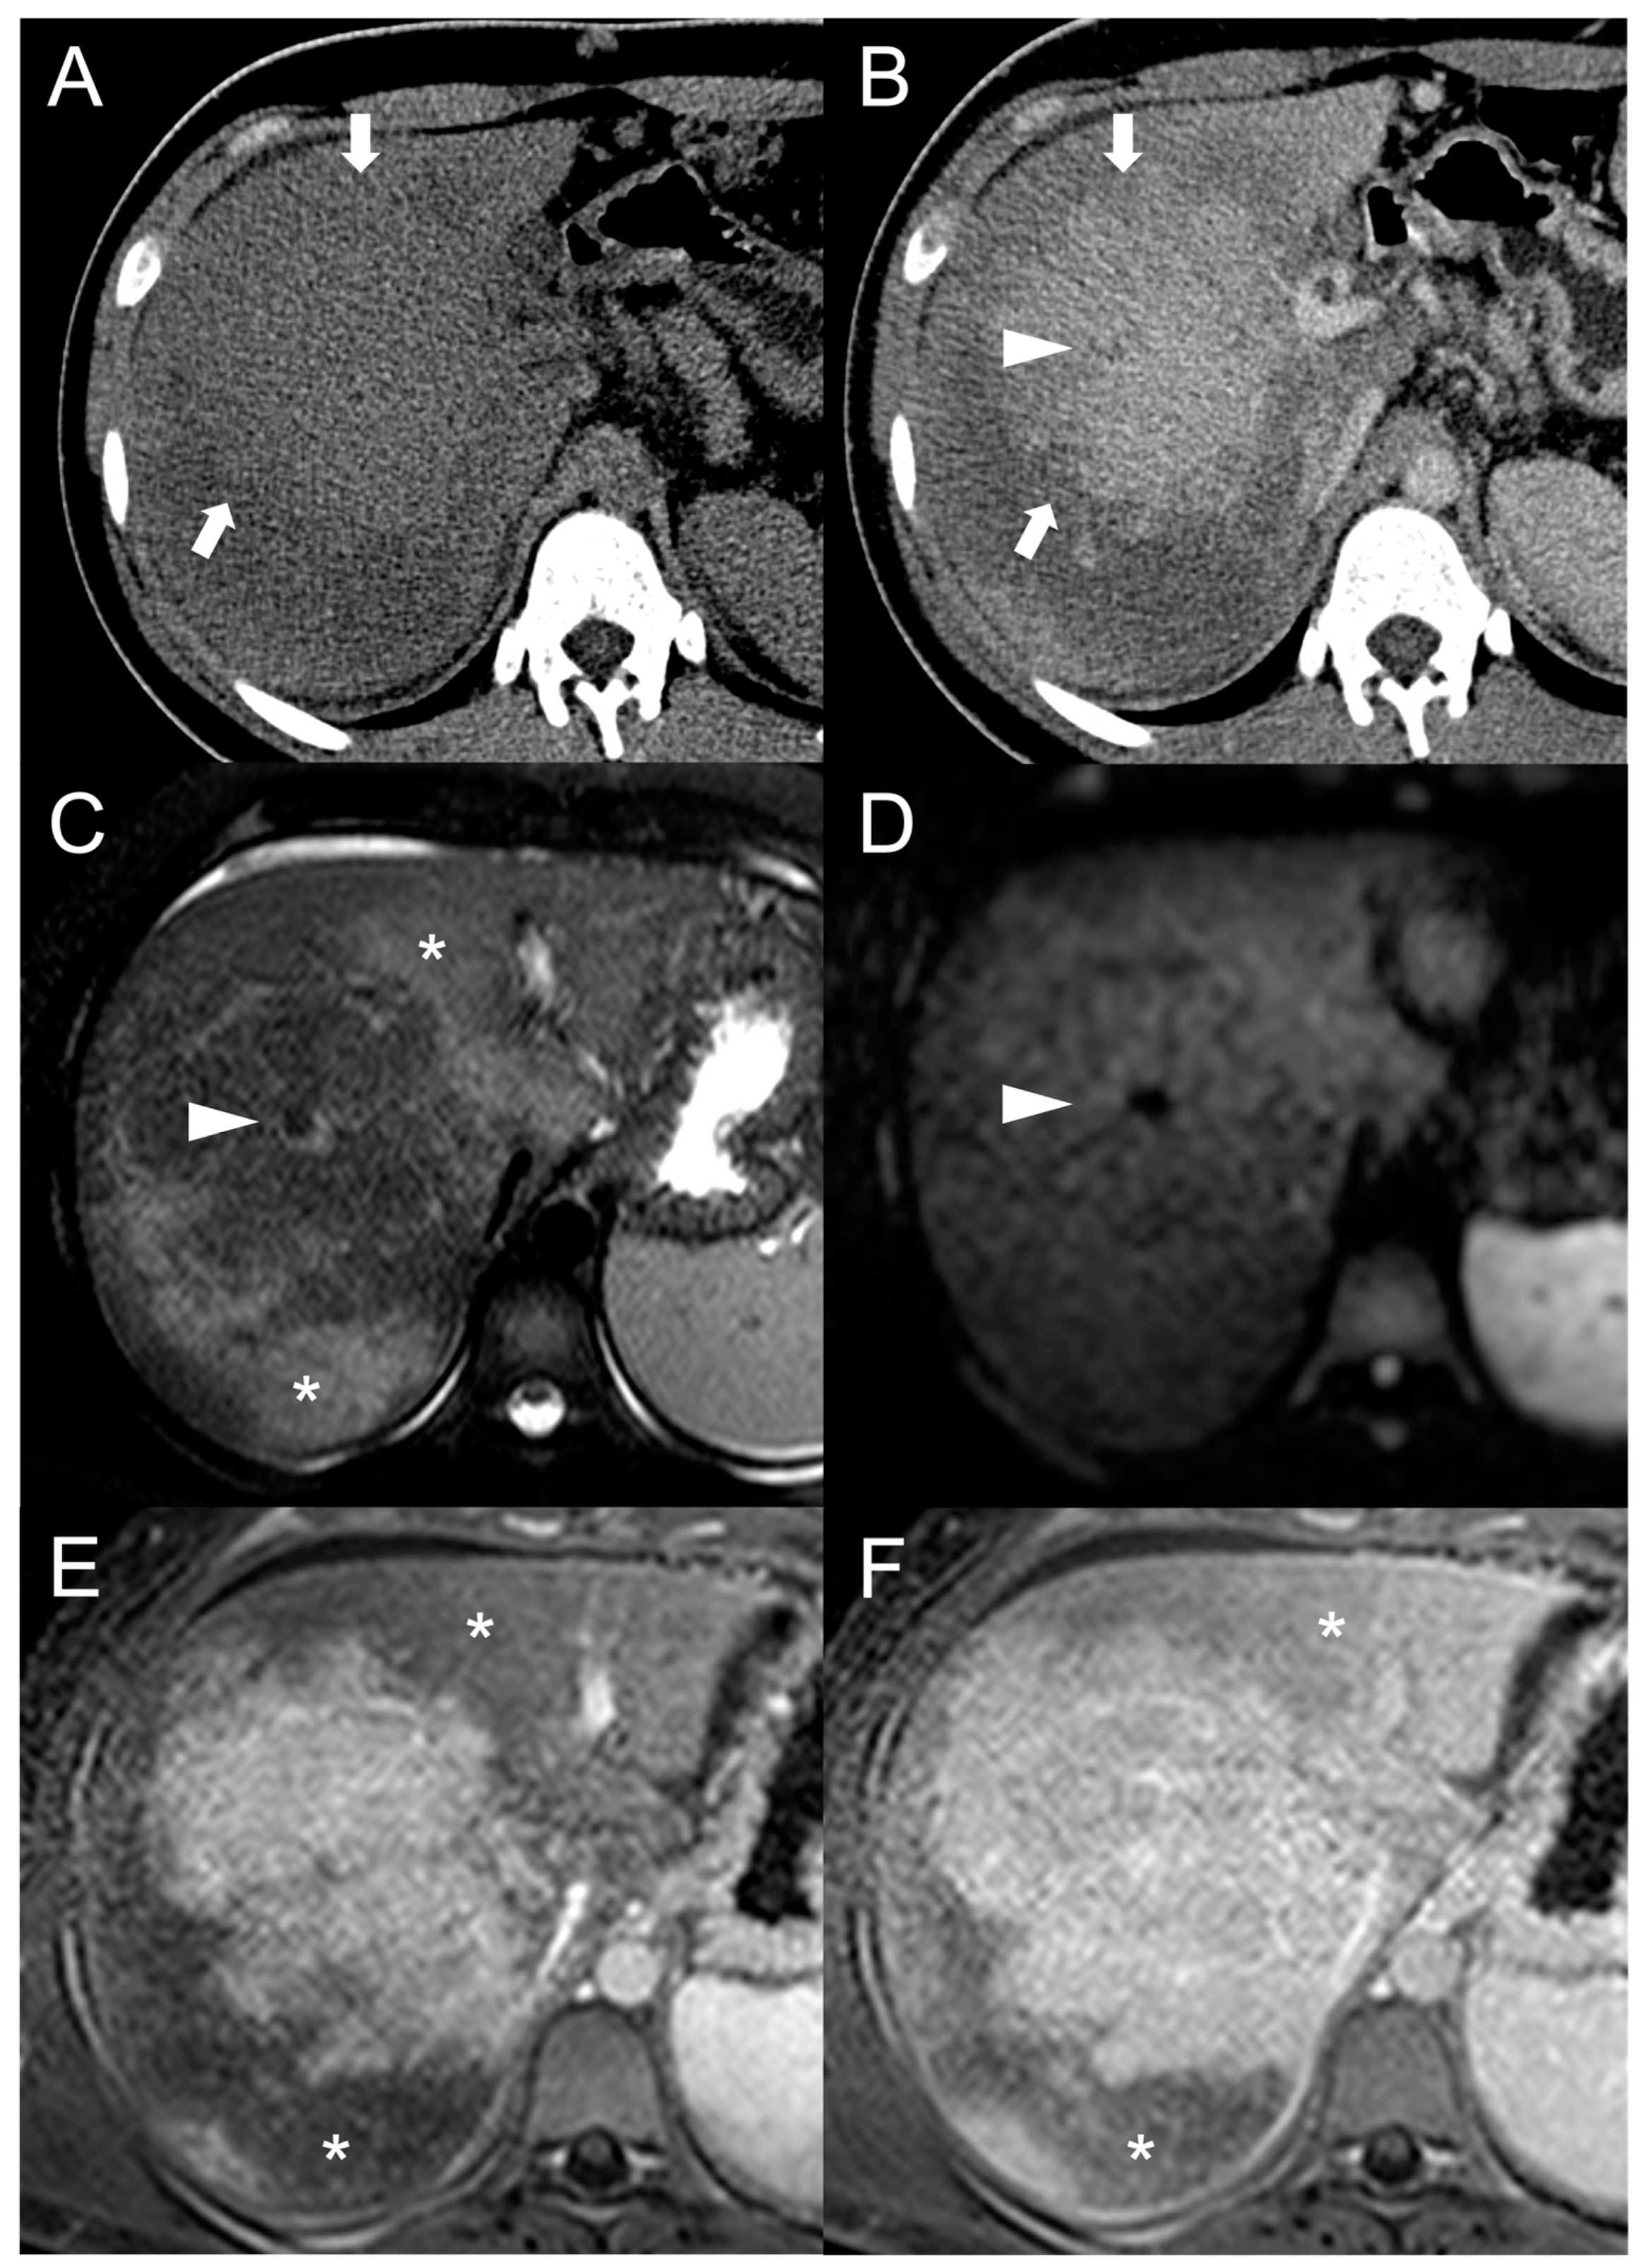

The presence of a central scar is another common finding in FNH-like RNs, particularly in those larger than 1 cm [10]. This scar typically appears as a hypointense, central stellate area on fat-suppressed T1-weighted imaging and a hyperintense area on T2-weighted imaging (Figure 2). Moreover, since regenerative nodules are made up of normal hepatocytes, they appear isointense or slightly hyperintense to the adjacent liver parenchyma on diffusion-weighted imaging, and there is no significant reduction in the diffusion values observed on the ADC map. These characteristics help to differentiate between regenerative and HCC nodules with reasonable confidence in patients with BCS.

Figure 2.

FNH-like RN with central scar (arrow) in a 34-year-old male patient with Budd–Chiari syndrome. In MRI, the scar is typically hyperintense on fat-saturated T2-weighted images (A) and hypointense in T1-weighted images (B). In the arterial phase after contrast agent administration, the scar can be identified as a central stellate area that appears hypodense in CT (C) and hypointense in MRI (D). In the CT delayed phase, the nodule shows increased density, but a central hypodense component representing the scar remains visible (E). In gradient-echo T1-weighted images acquired in the hepatobiliary phase (F), the scar is clearly depicted as a central low-signal area.

MRI features of FNH-like RNs are shown in Figure 3.

Figure 3.

MRI examination of a 29-year-old female with Budd–Chiari syndrome. On fat-saturated T2-weighted images (A) FNH-like RNs are barely discernable as they appear isointense to the liver parenchyma; occasionally, areas of very slightly hyperintense signal (arrow) can be identified, possibly related to congested nodules or central scar. On out-of-phase T1-weighted images (B) the presence of nodular lesions is more appreciable, as FNH-like RNs (arrow) appear slightly hyperintense compared to the surrounding liver parenchyma. On DWI (b-value = 600) (C), FNH-like RNs may show a slight heterogeneous hyperintensity due to central scar or congestion. On unenhanced gradient-echo T1-weighted images (D), the nodules (arrows) appear hyperintense, while on arterial phase (E) they show vivid enhancement with a peripheral hypointense rim due to hepatic tissue congestion. On portal venous (F) and delayed (G) phases, the nodules become progressively isointense to the liver. On the T1-weighted images (flip angle = 30°) in the hepatobiliary phase (H), FNH-like RNs show hyperintensity compared to the surrounding liver parenchyma.

Besides changes in size, as mentioned above, the MRI features of FNH-like RNs can alter during the follow-up period (Figure 4). For example, the T1 and T2 signal intensity may change, more frequently with a shift from hyperintense to isointense on T1-weighted images and from hypointense to isointense on T2-weighted images. The enhancement pattern may vary as well, with washout acquired in 8% of cases and lost in nearly 20% of cases.

Figure 4.

MRI examinations of a 31-year-old male patient with Budd-Chiari syndrome performed in 2016 (A), 2017 (B), 2018 (C), and 2020 (D). Gradient-echo T1-weighted sequences (flip angle = 30°) acquired in the hepatobiliary phase revealed a 25 mm FNH-like RN (arrows) with central scar and peripheral hyperintensity in 2016 (A). The lesion size grew to 41 mm after 1 year (B) and further to 44 mm after 2 years (C), but it reduced to 35 mm in 2020 (D). Additionally, new FNH-like RNs appeared over time (arrowheads in C,D).